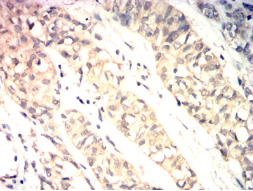

IHC    1/200 - 1/1000